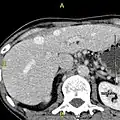

The diagnosis of liver disease is made by liver function tests, groups of blood tests, that can readily show the extent of liver damage. If infection is suspected, then other serological tests will be carried out. A physical examination of the liver can only reveal its size and any tenderness, and some form of imaging such as an ultrasound or CT scan may also be needed.[63] Sometimes a liver biopsy will be necessary, and a tissue sample is taken through a needle inserted into the skin just below the rib cage. This procedure may be helped by a sonographer providing ultrasound guidance to an interventional radiologist.[64]

Axial CT image showing anomalous hepatic veins coursing on the subcapsular anterior surface of the liver.[65]